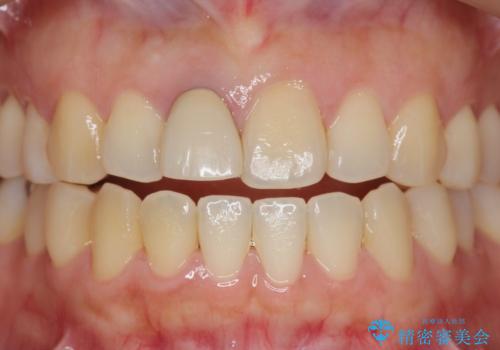

オーダーメイドで造る、自然な前歯セラミッククラウン

精密な仮歯をいれ、歯周組織を整えるとともにファイバーコア築盛、シェードテイキングを行い見た目に自然なジルコニアクラウンを製作していきます。

ジルコニアクラウンの中でも当法人のグレードの高い、スペシャル・エクセレントプランはオーダーメイドで色調を合わせることで周囲の歯に馴染んだ自然な歯を製作することのできるプランです。